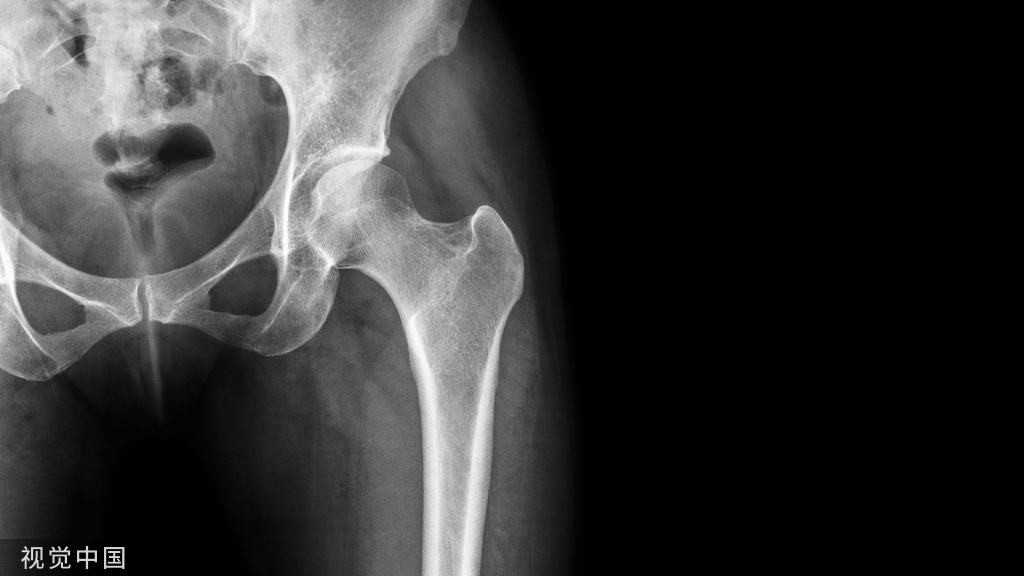

髋臼假体位置的准确测量对于评估全髋关节置换术后的预后具有重要意义。平片和CT扫描已被用来评估它的位置。结果表明,使用CT可以准确评估部件的位置;然而,由于CT扫描昂贵且使患者暴露在大量辐射中,x光平片仍被广泛使用。

为降低THA术后的脱位率,Lewinnek提出臼杯安全区的概念:影像学前倾角 (15±10°),外展角(40±10°),在安全区内的脱位率为1.5%,在安全区外的脱位率为6.1%,虽有争议但得到大多数学者认可。(4)